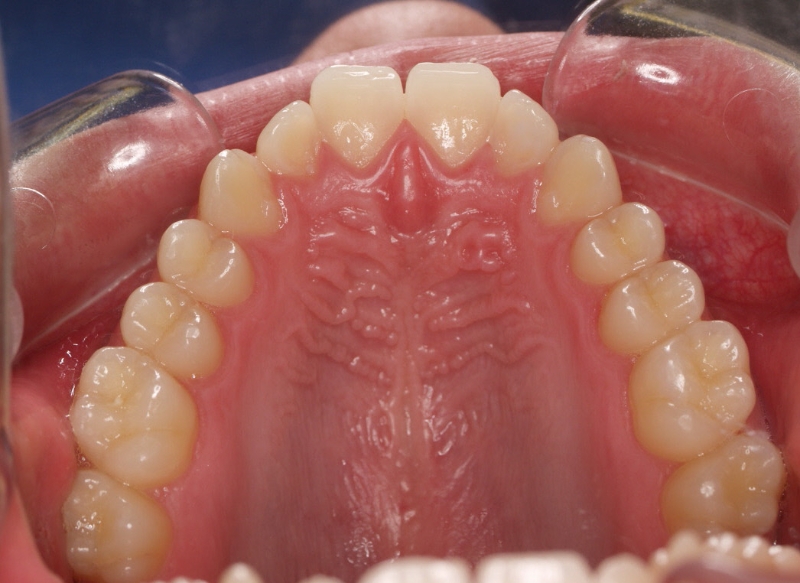

El stripping consiste en la reducción interproximal del esmalte entre los dientes posteriores y anteriores, así obtenemos espacio para alinear los dientes apiñados.

Chica de 17 años tratada en 1 año con stripping en los dientes inferiores